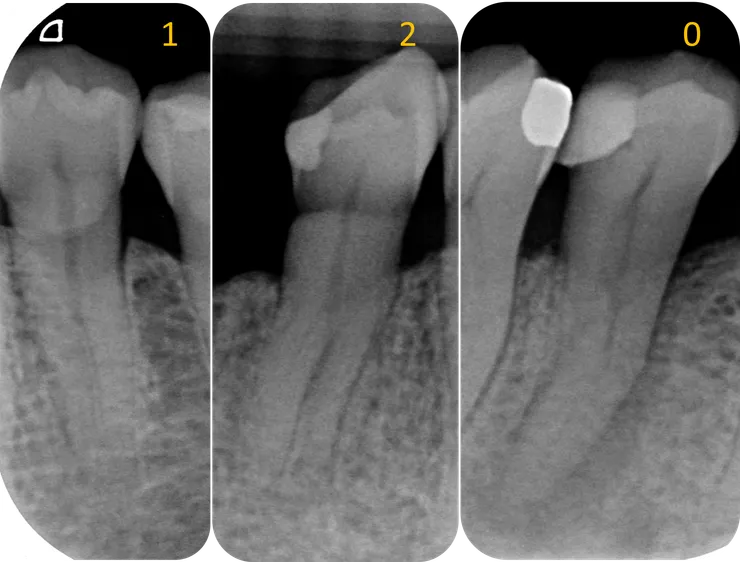

Case 1.

之前提到過 deep split canal 的特徵:

1. Double PDL line.

--> 由於這顆牙齒有 rotation, 所以重疊的那條 PDL line 轉到了中間來 (綠色箭頭所指),呈現出如同 下7 般的 C-shaped root 的樣子 (實際上它的 root form 也常常真的是 C-shape......)

2. Fast break.

--> 如紅色箭頭所指處,canal 在此處忽然看不見,顯示此處可能有個分岔。

3. 轉診醫師覺得有兩個 canal 但其中一個 canal 置入有困難。

--> 如右邊那張 X 光片所示。